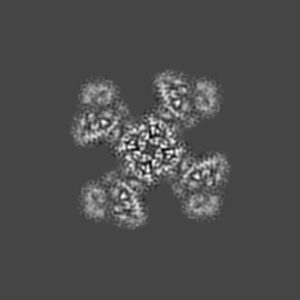

Structure of pancreatic ATP-sensitive potassium channel bound with glibenclamide and ATPgammaS (3D class1 at 4.33A)

Sample Organism: Mus musculus, Mesocricetus auratus

Sample: KATP

Fitted models: 5ykf

Ligand binding and conformational changes of SUR1 subunit in pancreatic ATP-sensitive potassium channels.

Wu JX, Ding D, Wang M, Kang Y , Zeng X, Chen L

(2018) Protein Cell , 9 , 553 - 567